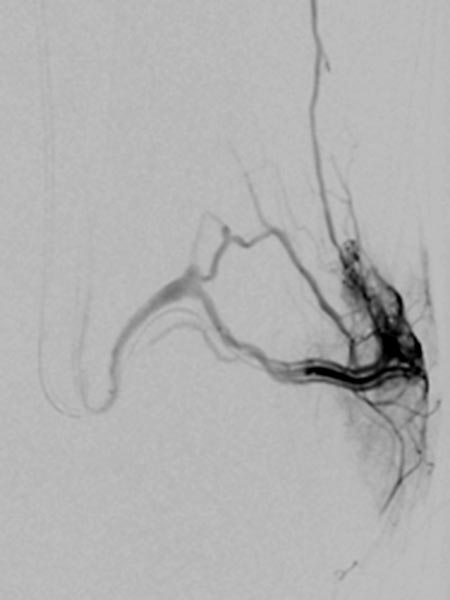

Superselective digital subtraction angiography via a microcatheter in the superior gluteal artery in a distal branch. The nidus of the fine fistulous arteriovenous malformation shows such fine shunts that they can hardly be resolved anatomically on angiography.

During embolization via the microcatheter (not shown) using the roadmap technique, the embolic agent (ethylene-vinyl alcohol copolymer) is pushed forward into the nidus and further into the venous outflow of the AVM to close even the smallest fistulas ("plug & push" technique).